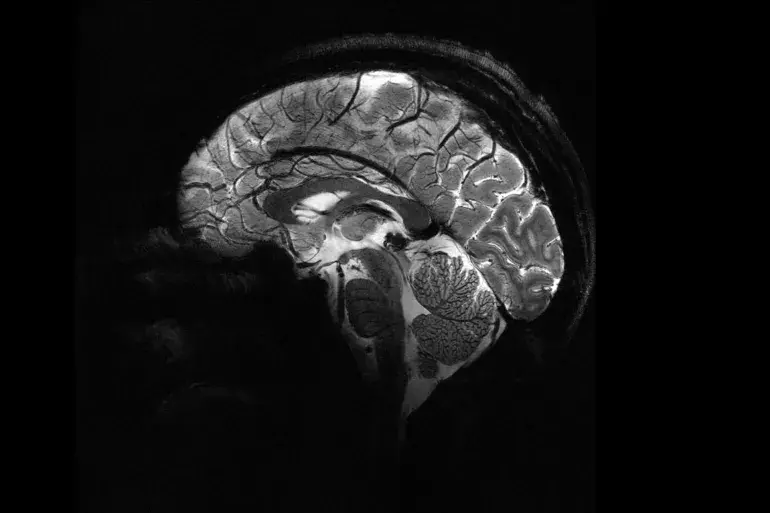

Самое точное изображение мозга с использованием мощнейших магнитно-резонансных томографов.

Проведенное Французским агентством по атомной энергии самое точное изображение мозга человека после получения разрешения на использование самого мощного магнитно-резонансного томографа. Власти затягивали с выдачей разрешения, после того как устройство впервые было использовано в 2021 году для съемки тыквы, но в последние месяцы пришло около 20 добровольцев, чтобы стать первыми, кто попробует устройство, которое теперь находится в зоне Плато де Сакла-юг Парижа, где расположены множество технологических компаний и университетских резиденций.

Физик Александр Вигнод говорит, что им удалось достичь степени точности, которой ранее не удавалось добиться. Интенсивность магнитного поля, создаваемого устройством, составляет около 11,7 тесла, и это позволяет устройству выполнять сканирование точнее на порядок по сравнению с типичными магнитно-резонансными томографами в больницах, мощность которых обычно не превышает 3 тесла.

Сравнивая несколько снимков, сделанных современным устройством, с другими сделанными обычными магнитно-резонансными томографами, Вигнод говорит, что, используя мощный сканер, им удалось увидеть маленькие сосуды, питающие кору мозга, а также обнаружить детали мозжечка, которые ранее скрылись от взгляда.

Физик и министр по вопросам исследований во Франции Сильви Врейтель говорит, что степень точности нельзя оценить словами, и этот успех поможет лучше лечить и выявлять многие заболевания мозга, а также поможет в ранней диагностике.